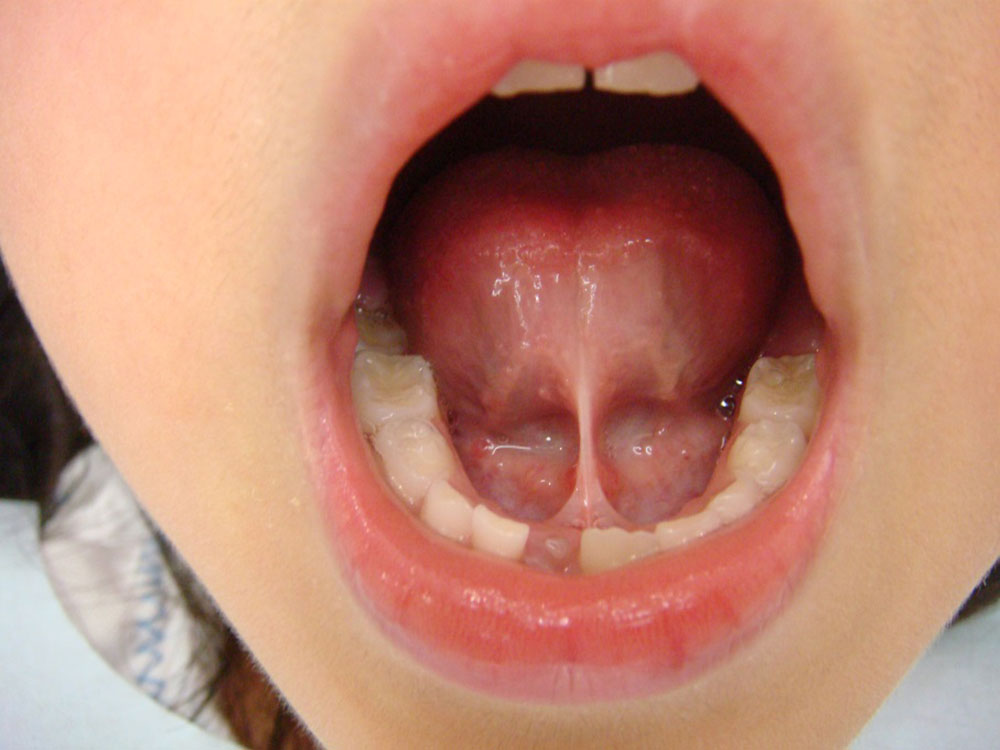

舌小帯(ぜつしょうたい)は、舌の裏側にある「すじ」のことです。この小帯が短いことを乳幼児健診等で指摘されることがあります。

舌小帯異常などは、舌強直症といって、舌の運動障害を起こしてしまいます。舌尖部を使って発音するサ行、タ行、ラ行の構音障害や、摂取障害などがあります。これも、手術しなければなりません。また、成長してから、発音他に影響がある場合は切除をおこなうこともあります。

正常な舌との比較